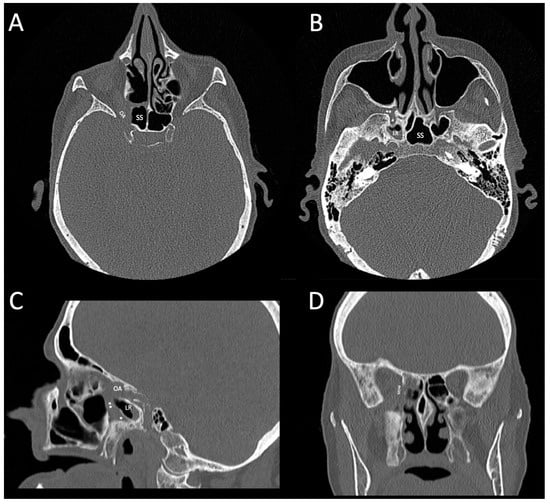

2. Case Presentation

2.2. Revisional Treatment

2.3. Follow-Up and Outcome